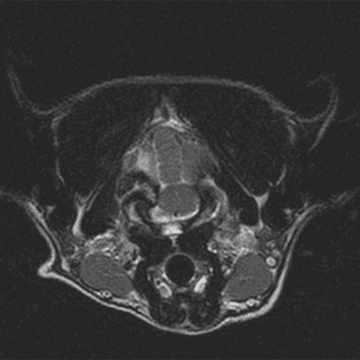

High-field MRI of Milo’s brain was performed in multiple planes and sequences including T2W, T1W, and FLAIR, and IV contrast was administered. A skeletal fragment causing compression of the left cerebellar hemisphere and brainstem was discovered, with T2 hyperintensity of the adjacent cerebellar tissue and T1 isointense material filling the left tympanic bulla.

In summary, MRI and CT revealed a fracture of the occipital bone at the back of the skull, which was compressing the cerebellum and brainstem, and also a fracture of the occipital condyle, where the skull connects to the first vertebra (AO luxation).